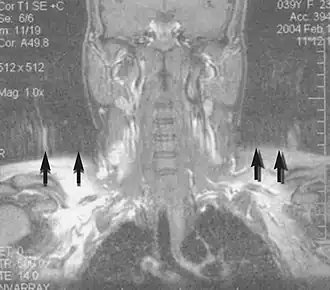

Angiography

Magnetic resonance angiography (MRA) generates pictures of the arteries to evaluate them for stenosis (abnormal narrowing) or aneurysms (vessel wall dilatations, at risk of rupture). MRA is often used to evaluate the arteries of the neck and brain, the thoracic and abdominal aorta, the renal arteries, and the legs (called a "run-off"). A variety of techniques can be used to generate the pictures, such as administration of a paramagnetic contrast agent (gadolinium) or using a technique known as "flow-related enhancement" (e.g., 2D and 3D time-of-flight sequences), where most of the signal on an image is due to blood that recently moved into that plane (see also FLASH MRI).[53]

Techniques involving phase accumulation (known as phase contrast angiography) can also be used to generate flow velocity maps easily and accurately. Magnetic resonance venography (MRV) is a similar procedure that is used to image veins. In this method, the tissue is now excited inferiorly, while the signal is gathered in the plane immediately superior to the excitation plane—thus imaging the venous blood that recently moved from the excited plane.[54]